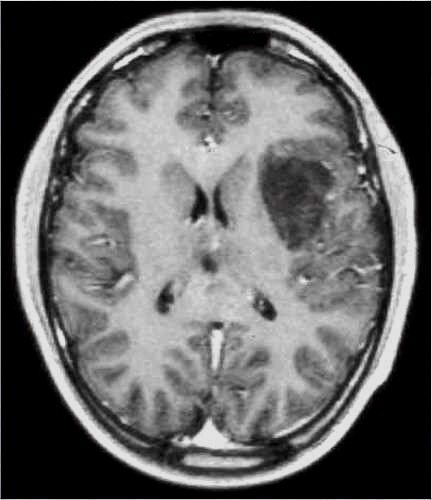

TC preoperatoria

TC postoperatoria

RM preoperatoria

RM postoperatoria